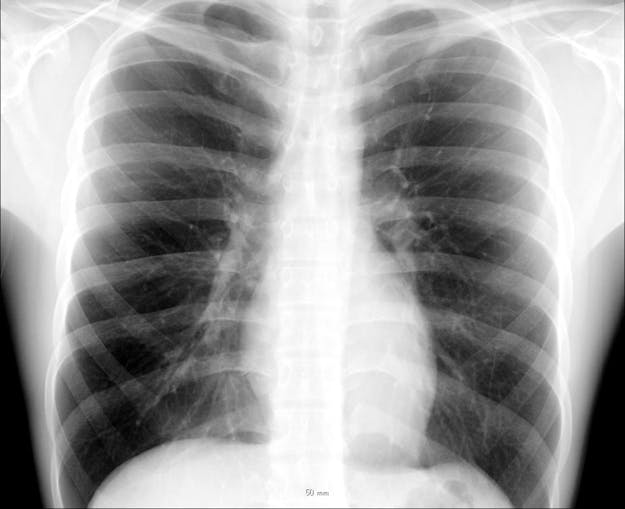

De opmars van AI in de medische beeldanalyse begon al in 1998, vertelt Van Ginneken. Toen werd voor het eerst software voor borstkankerscreening goedgekeurd door de Amerikaanse waakhond FDA. “Dat werkte toen nog niet eens zo heel goed”, zegt hij. De echte sprong kwam pas in 2012, toen AlexNet, een neuraal netwerk, een AI-wedstrijd won. Dit type algoritme was veel beter in staat om objecten op plaatjes te herkennen dan algoritmes die tot dan toe werden gebruikt. “Het versloeg de traditionele methode met zo’n grote marge dat de wedstrijdorganisatie zich afvroeg of er een fout zat in hun scoresysteem, maar dat was niet zo.” Deze techniek bleek goed toepasbaar op medische beeldanalyse en kon afwijkingen in verschillende lichaamsdelen steeds beter opsporen. Van Ginneken heeft daarmee bijvoorbeeld software gemaakt die tuberculose in de borstkas en afwijkingen op longfoto’s kan opsporen.

Een röntgenfoto van de borstkas en longen.

Chikumaya, CC BY-SA 3.0 via Wikimedia CommonsDe laatste jaren is er nog een tweede grote AI-ontwikkeling bijgekomen die de medische wereld op zijn kop zal zetten, denkt Van Ginneken. Dat zijn de zogeheten transformermodellen, waarop programma’s als ChatGPT zijn gebaseerd. Deze programma’s zijn heel goed in het verwerken van grote hoeveelheden informatie. “In het ziekenhuis wordt continu van alles gemeten, zoals je hartslag, bloeddruk en bloedwaarden, en er worden scans gemaakt. Daarnaast is er een medisch dossier, waarin artsen en verplegend personeel aantekeningen maken. Zo ontstaat er een mix van heel veel verschillende soorten data, uit teksten, sensoren en beelden. Ook verschijnt er dagelijks nieuwe medische literatuur. Voor een arts is het onmogelijk om dat zelf allemaal bij te houden en orde te scheppen in die chaos. Nu hebben we computers die heel goed teksten uit het dossier kunnen samenvatten en die op basis van al die data een advies voor een behandeling kunnen geven.” Van Ginneken en zijn collega’s hebben dat al in de praktijk getest. Zij vroegen ChatGPT om een eerste diagnose te geven aan dertig patiënten op de SEH (spoedeisende hulp) van het Jeroen Bosch Ziekenhuis in Den Bosch. “We waren stomverbaasd dat de software even goed presteerde als de artsen in het ziekenhuis.”